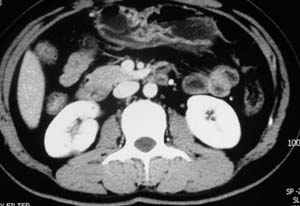

以下是引用子期在2010-3-19 20:47:00的发言:[br]血管畸形的ct增强应该有明显强化,本例并不相符合。本例双肾局部的略低密度影,累及肾盂,局部皮质明显变薄、内陷,增强扫描有轻度的强化,应考虑为炎性病变,患者为年轻男性,累及双肾的感染以结核较常见,可以没有明显的临床症状,尿中有时候也并不能查出什么;肾脓肿常有明显感染中毒症状,本例不符,另外一般的肾盂肾炎或肾小球肾炎通过小便就可确诊,其它还不能排除的是黄色肉芽肿性肾盂肾炎,然而单凭ct一般也很难鉴别。